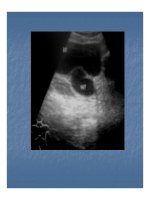

Siêu âm

Hình túi nước tiểu liên tục với niệu quản, thành mỏng lồi

vào lịng bàng quang, khơng thấy hình luồng nước tiểu

phụt vào bàng quang (bên lành vẫn thấy).

Nếu chức năng thận cịn, có thể thấy túi thay đổi kích

thước khi luồng nước tiểu dồn xuống.

Nước tiểu có thể trong hay khơng, có thể có sỏi trong túi

sa lồi.

Niệu quản thường giãn, nhu mô thận mỏng, giãn cả đài

bể thận, và niệu quản nếu ở mức độ nặng